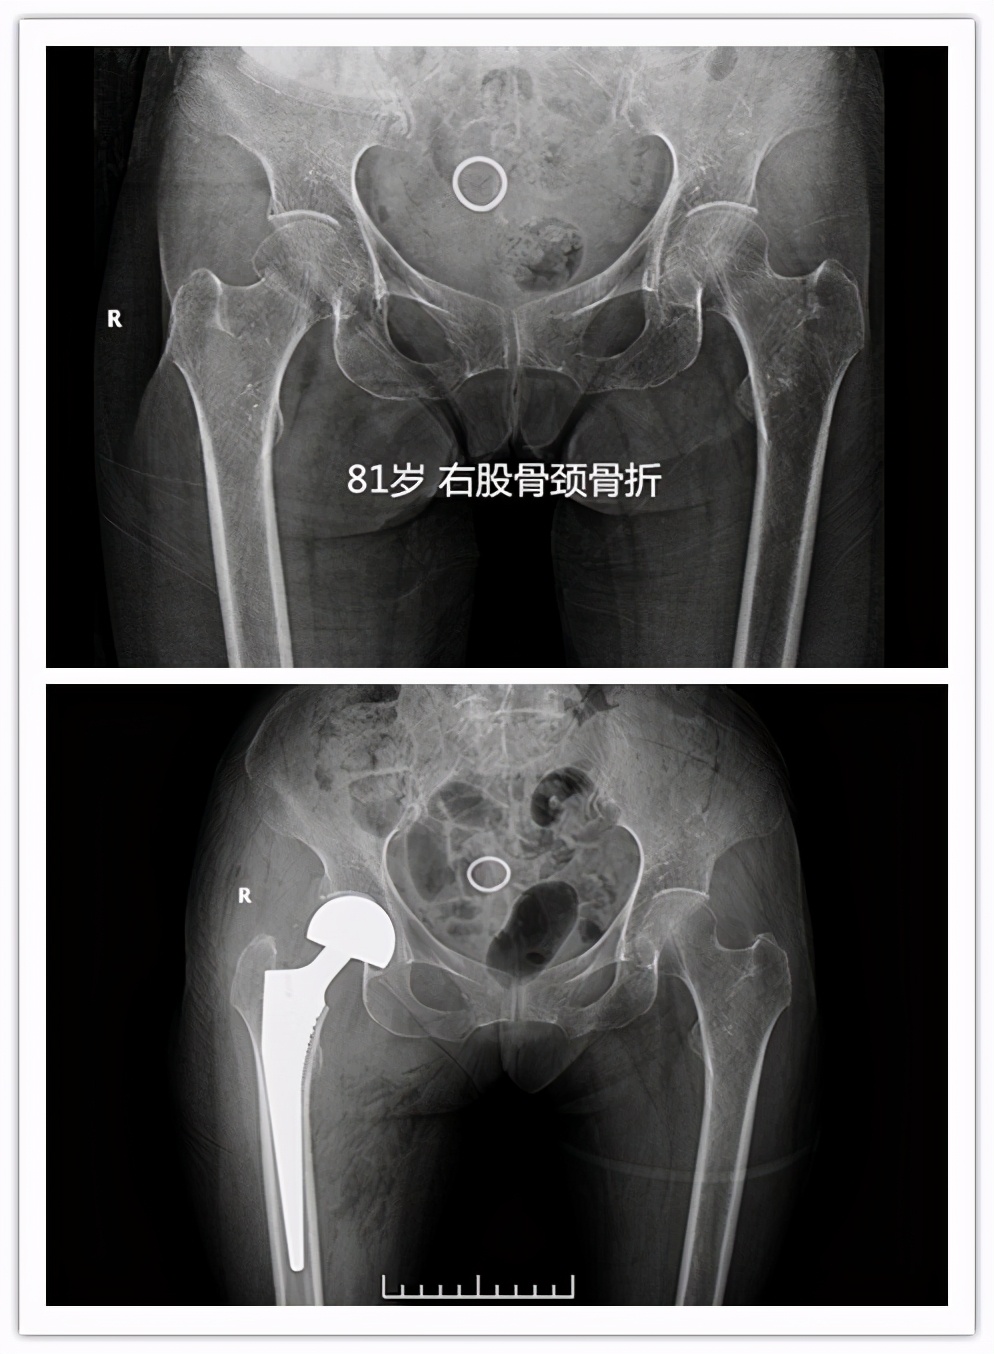

答案就是指 老年人髋部骨折 ,也就是东北话常说的“ 胯骨轴摔坏了 ”,包括股骨颈及粗隆间骨折。这个部位骨折后病人因轻微活动便会诱发较剧烈的疼痛,通常无法坐起、翻身困难,需长期卧床,只有一少部分骨折无移位或者骨折断端嵌插的病人,经2-3个月的卧床后出现骨折愈合后可能恢复行走功能,其余病人可能因骨折不愈合、畸形愈合等丧失行走功能。长期卧床面临着肺内感染、坠积性肺炎、褥疮、下肢静脉血栓、泌尿系感染等并发症, 据统计约50%的患者因卧床出现相关并发症在1年内死亡 ,所以被称作“人生最后一次骨折”。

这种骨折出现了怎么治疗呢?其治疗方法分为手术内固定治疗(如空心钉、PFNA、INTER- tan等等)或者人工关节置换手术治疗。

- 针对老年高龄的股骨颈骨折患者,一般可能人工股骨头置换手术,手术时间短,术后1-2日病人可早期下床活动,降低卧床并发症,提高患者生活治疗。针对粗隆间骨折,可行PFNA或者人工股骨头置换手术。

很多家属最大疑问:我们家的老人都七八十岁了,还能做手术吗?其实跌倒后出现髋部骨折多大出现于老年高龄患者,近两年我们科室做的因股骨颈骨折行人工股骨头置换手术最大年龄为 99岁 ,老人家术后2日扶助行器下床活动。 所以老人是否能耐受手术,不能只看年龄 ,需要请医师进一步进行术前评估。通过手术治疗,病人可尽早离开床,尽快恢复日常生活,提高患者生活质量,降低死亡率。